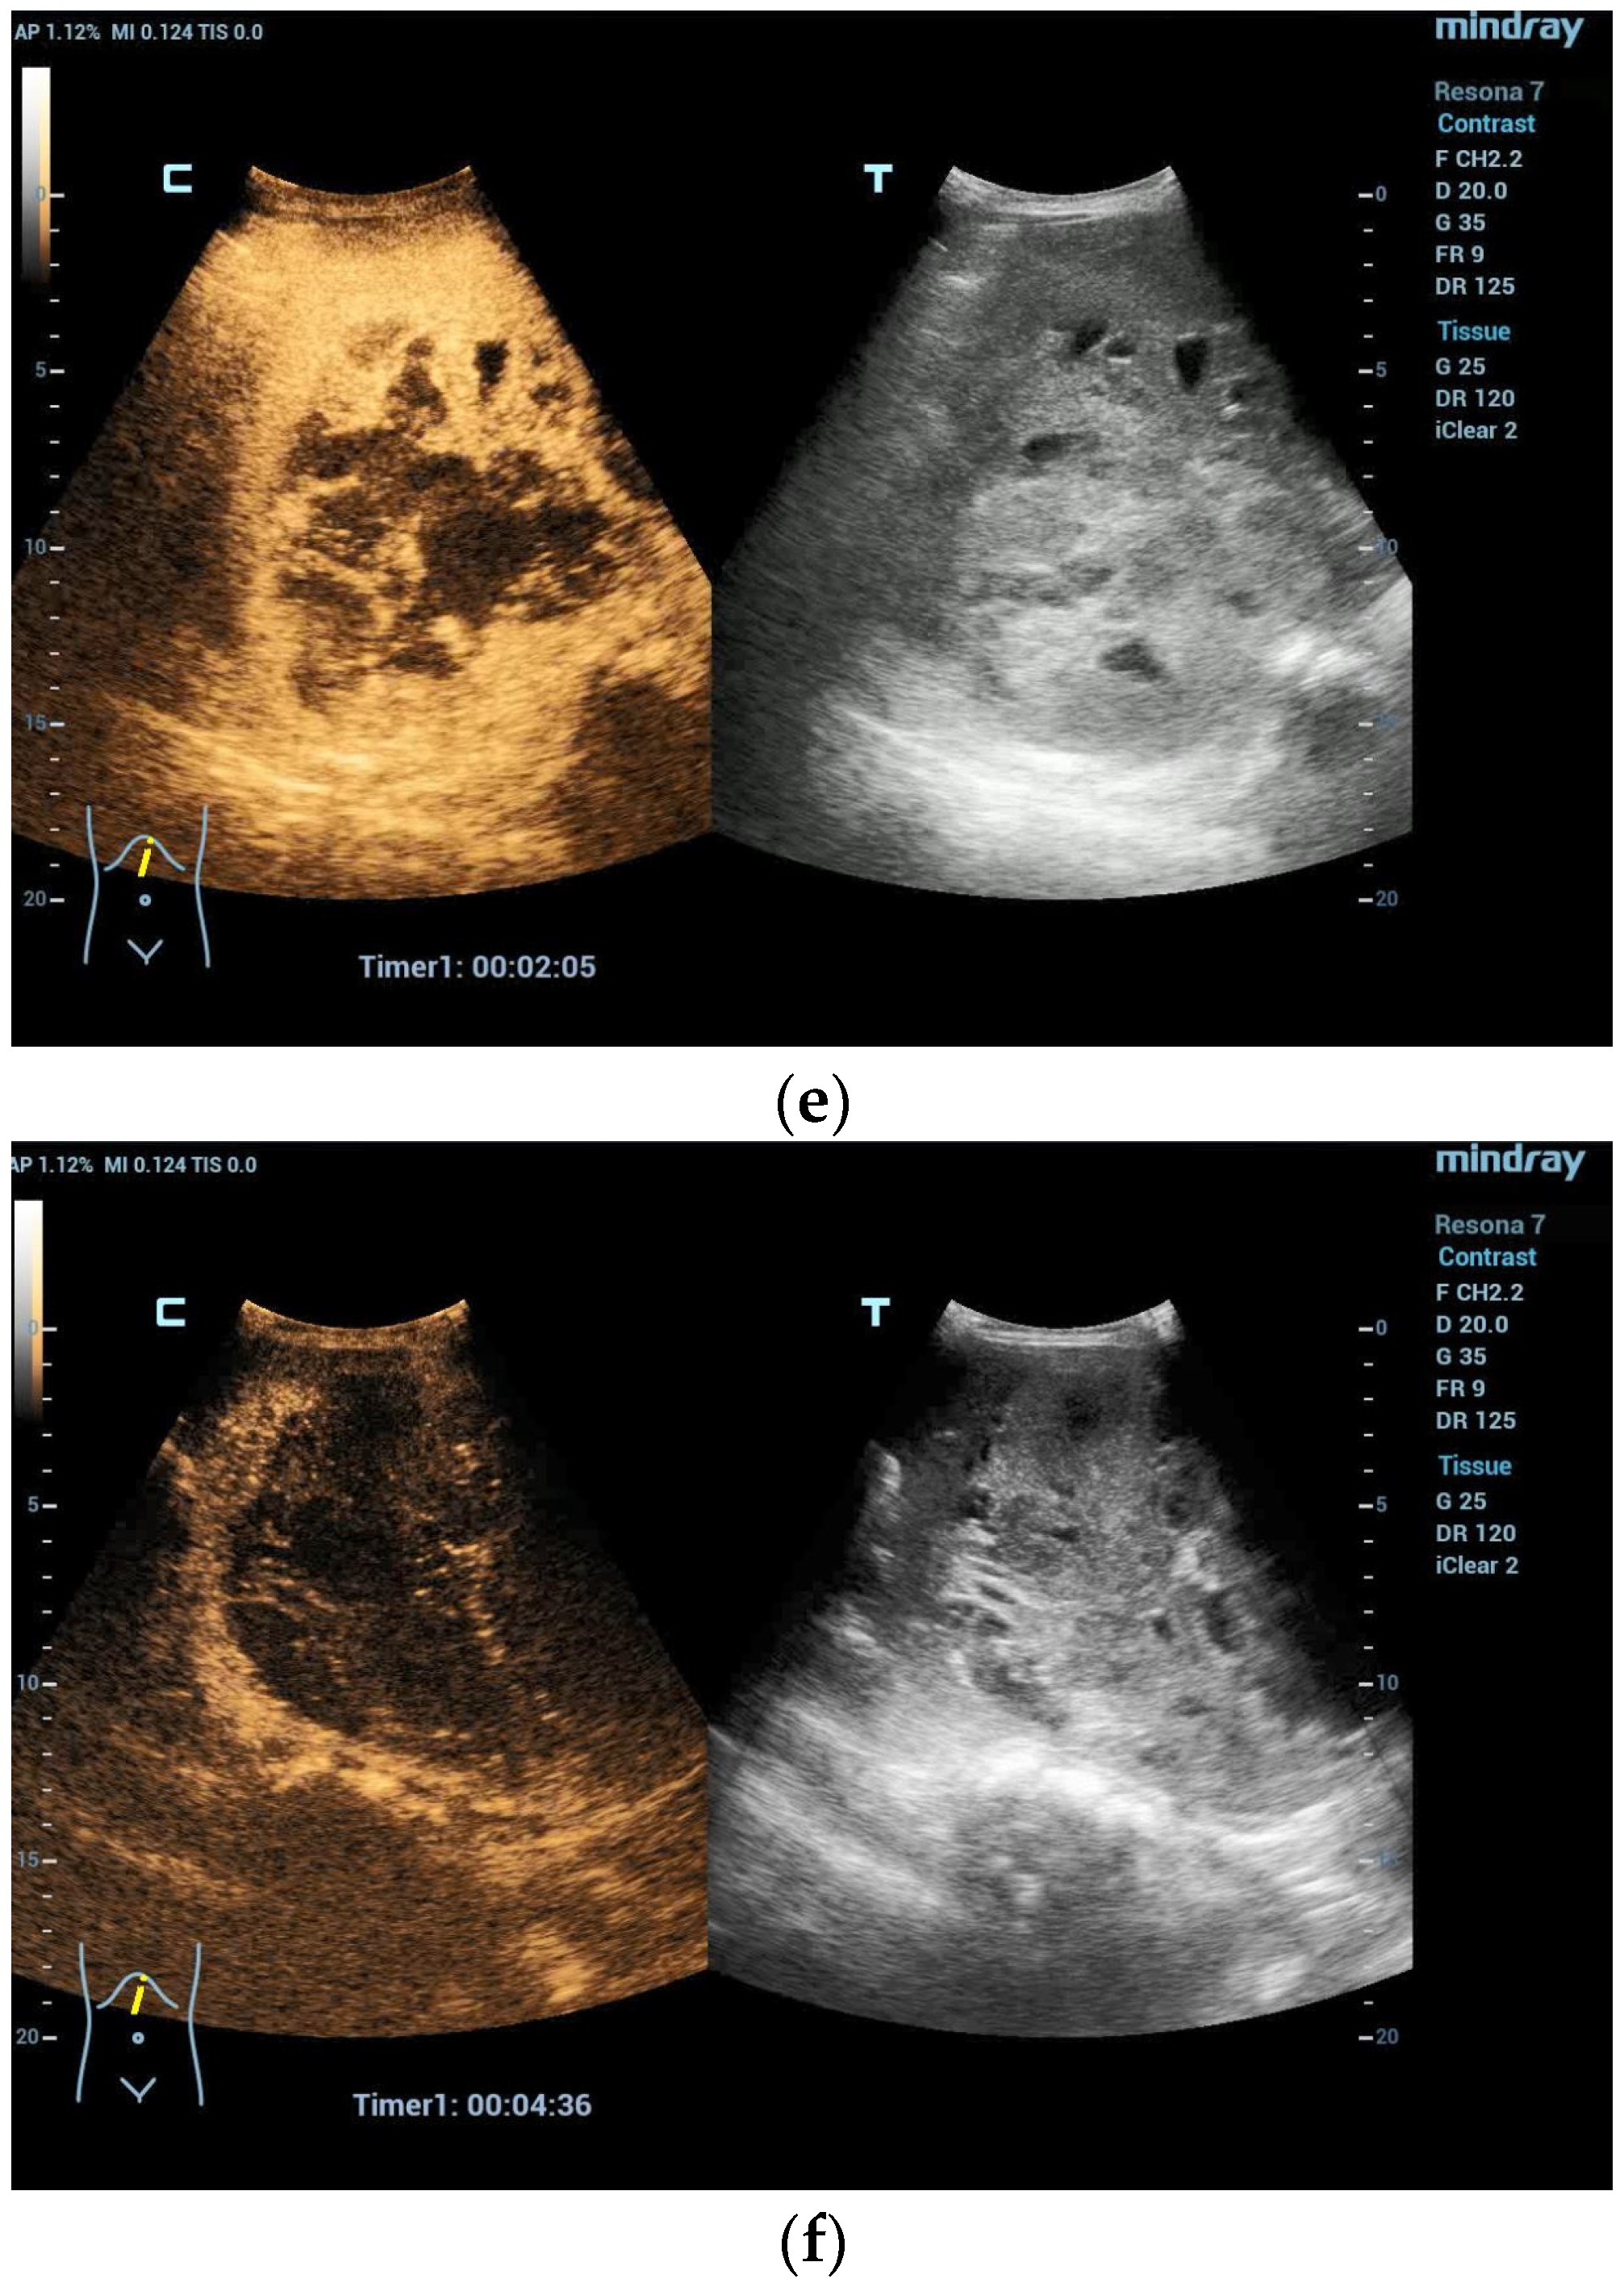

Figure 3.

Hemangioendothelioma in a 1-month-old infant. A cystic mass with a maximum diameter of 4 cm in liver segment IV with blurred borders and calcifications with dorsal acoustic shadow (a–e). Evidence of increased vascularization on color Doppler (f). Feeder artery with inflow from the hepatic artery and venous outflow via the markedly dilated left hepatic vein (g). Increased flow velocities in the coeliac trunk and hepatic artery (h,i). Outflowing left hepatic vein with arterialized flow profile and increased flow velocities (j).